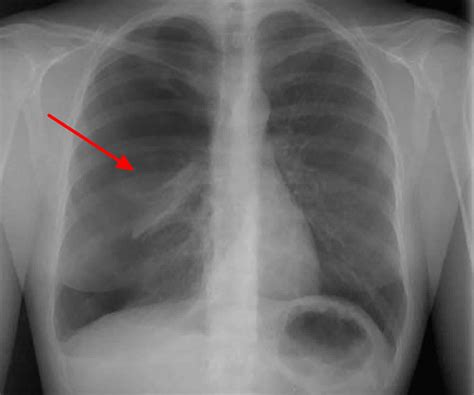

Alright, let’s kick things off with pneumothorax . Basically, guys, it’s when air gets into the space between your lung and your chest wall. You know that space? It’s called the pleural space, and normally it’s a pretty tight seal. When air leaks into it, it pushes on the outside of your lung, making it collapse, either partially or totally. Think of it like a balloon deflating because it’s been poked. This condition can happen for a few reasons. Sometimes, it’s spontaneous, meaning it just happens without any obvious cause – this is more common in tall, thin young men, kinda weird but true! Other times, it’s caused by an injury, like a direct blow to the chest, a car accident, or even during certain medical procedures like inserting a central line or a biopsy. Even severe coughing fits can sometimes do it. The main symptom you’ll notice is a sudden, sharp chest pain that often gets worse when you take a deep breath or cough. You might also experience shortness of breath , which can range from mild to severe depending on how much your lung has collapsed. Some folks also feel a tightness in their chest. The diagnosis usually involves a physical exam where a doctor might hear decreased breath sounds on the affected side, and then definitely a chest X-ray , which is the gold standard for spotting that tell-tale collapsed lung. Treatment varies; small, spontaneous pneumothoraces might resolve on their own, while larger ones or those causing significant symptoms usually require a chest tube to remove the air and re-inflate the lung. It’s all about getting that pressure off the lung so it can do its job again.

So, how do doctors figure out if it’s air or pus causing the trouble? For pneumothorax , the diagnosis is usually pretty straightforward once symptoms arise. A physical examination is the first step. The doctor will listen to your lungs with a stethoscope and might notice decreased or absent breath sounds on the affected side. They’ll also check your vital signs, like heart rate and oxygen levels. The absolute star of the show for diagnosing pneumothorax is the chest X-ray . It clearly shows the collapsed lung and the air in the pleural space. In some cases, especially if the diagnosis isn’t clear on X-ray or if there’s suspicion of other lung issues, a CT scan might be used. It provides a more detailed view of the chest cavity. For diagnosis, we are looking for that distinct line of the collapsed lung margin and the absence of lung markings beyond that line, indicating air.